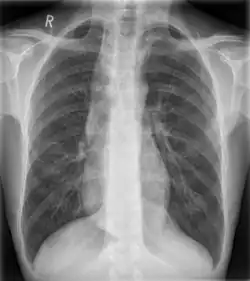

Die Erkrankung schreitet vom ersten zum letzten Stadium fort. Im Stadium I ist die Speiseröhre noch funktionsfähig und versucht gegen den zu hohen Druck im unteren Schließmuskel (Mageneingang) „anzupumpen“ (hypermotil = überbeweglich im Sinne von überaktiv). Im zweiten Stadium wird die Ösophagusmuskulatur bereits träger, da sich die Speiseröhre allmählich ausweitet (dilatiert). Im Endstadium der Erkrankung (Stadium III) „hängt“ die Speiseröhre schließlich als schlaffer funktionsloser Muskelschlauch im Mediastinum (Mittelfellraum des Brustkorbes). Die Speiseröhre ist defekt und vollkommen amotil (unbeweglich).

Im Frühstadium ist die Manometrie (Druckmessung) in unterschiedlichen Abschnitten der Speiseröhre die Methode der Wahl (Norm: 18–24 mmHg). Im Rahmen dieser Manometrie kann man die unzureichende Relaxation (Öffnung) des unteren Speiseröhrenschließmuskels in der Kombination mit einer Pumpfunktionsstörung der Speiseröhre oberhalb des Schließmuskels feststellen; im Spätstadium zeigt die Röntgenuntersuchung mit Kontrast-Schluckbrei (Barium-Brei) charakteristische Befunde. Dennoch kann man sich nicht auf diese Untersuchungen alleine verlassen, wenn man auch andere Ursachen einer Schluckstörung ausschließen möchte (z. B. Karzinome, Narbenstrikturen, neurologische Störungen, selten Dysphagia lusoria, Sklerodermie, Megaösophagus bei Chagas-Krankheit). Somit ist auch eine Endoskopie des oberen Verdauungstraktes, bzw. eine Gastroskopie (Magenspiegelung) in der Routinediagnostik zu fordern.